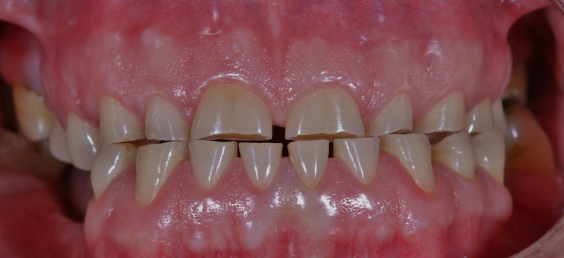

Atricija je gubitak tvrdih zubnih tkiva uzrokovan kontaktom zuba o zub za vrijeme funkcijskih ili parafunkcijskih smetnji.

Razlikujemo fiziološku, interproksimalnu te inteziviranu i patološku atriciju.

Fiziološku atriciju karakteriše jednakomjerno i fiziološko trošenje tvrdih zubnih tkiva zuba čitave denticije. Najprije se troše incizalni bridovi sjekutića uz nestanak incizalnih brazda, a zatim se troše okluzijske plohe kutnjaka te na kraju palatinalne kvržice gornjih i bukalne kvržice donjih kutnjaka. Zubi su u alveoli normalno fiziološki pokretljivi, a žvakanjem se međusobno taru što vremenom dovodi do izmjene kontakta iz tačkastih u plošne. Nastale brusne fasete su glatke, sjajne i ovalne. Skraćenje zubnog luka u osobe stare oko 40 godina moguće je za oko 1 cm u gornje te 7 mm kod donje vilice. Interproksimalnom abrazijom zuba se sužavaju i pomiču mezijalo.

Intezivirana i patološka atricija se javlja kod različitih stanja poremećaja mineralizacije (amelogenesis i dentinogenesis imperfekta) i parafunkcija (bruksizam). Trošenje može biti generalizovano ili lokalizovano (najčešće patološke etiologije zbog restauracije ili loše navike).